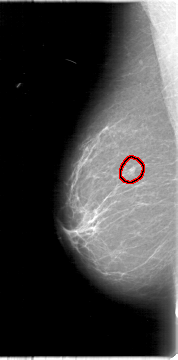

D_4009_1.RIGHT_MLO

RIGHT_MLO LINES 5386 PIXELS_PER_LINE 2656 BITS_PER_PIXEL 12 RESOLUTION 43.5 OVERLAY

FILE: D_4009_1.RIGHT_MLO.OVERLAY

TOTAL_ABNORMALITIES 1

ABNORMALITY 1

LESION_TYPE MASS SHAPE LOBULATED MARGINS OBSCURED

ASSESSMENT 0

SUBTLETY 4

PATHOLOGY BENIGN

TOTAL_OUTLINES 1

BOUNDARY